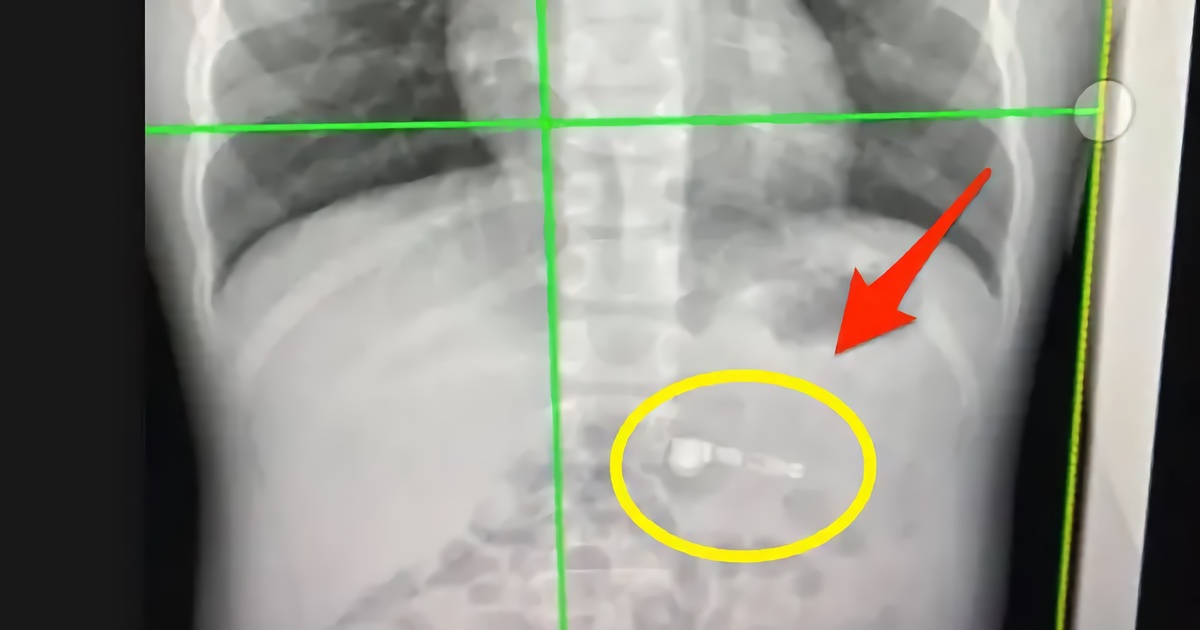

Девушка рассказала в своём TikTok-видео о случае, когда она перепутала таблетку ибупрофена с гаджетом Apple. В итоге она проглотила наушник, который не смогла извлечь из своего организма даже рвотой.